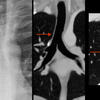

Paratracheal stripe